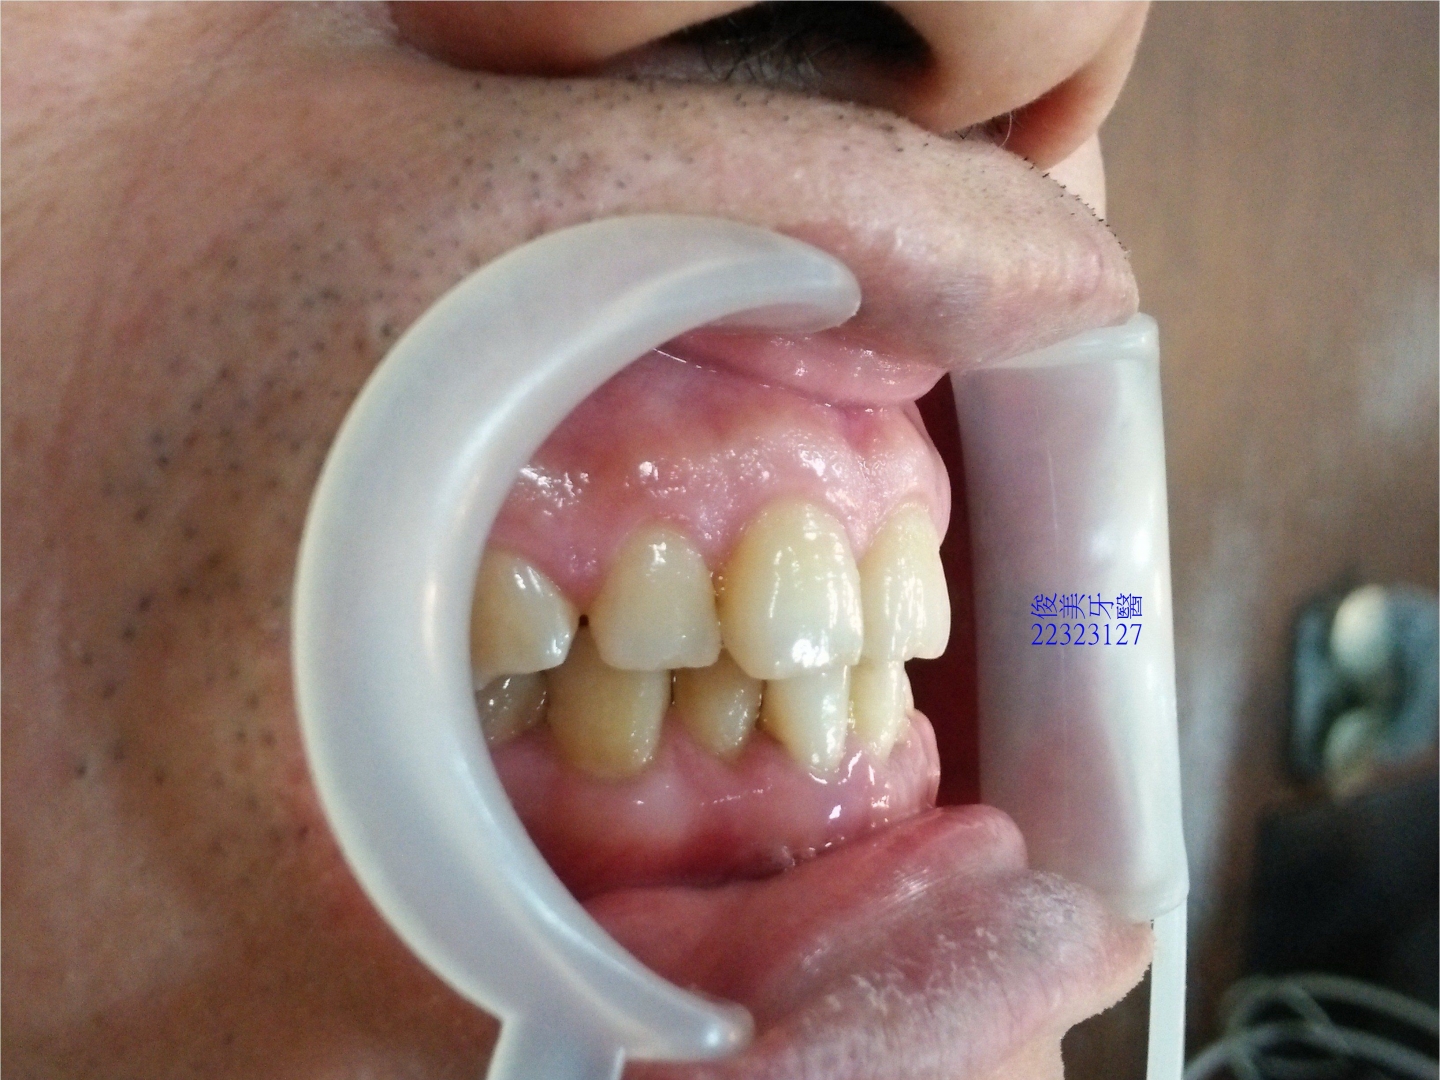

上顎原始狀況。

後牙咬合高度逐漸變低。

後牙咬合高度逐漸變低;犬齒受力大,高度剩下2/3,切端皆已磨損喪失。